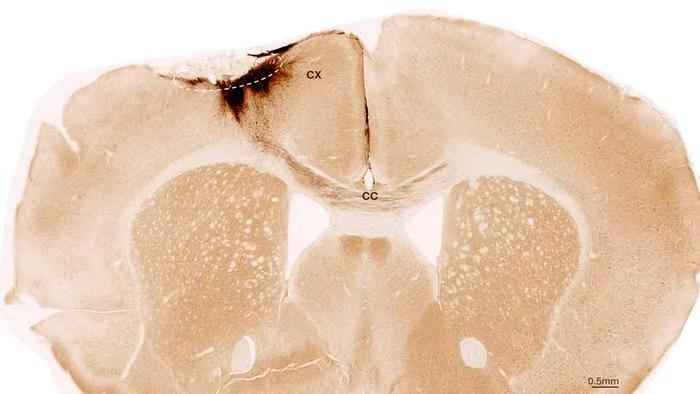

一种有潜力的替代治疗方法是利用干细胞再生软骨。需要注意的是,并非所有类型的干细胞都能生成软骨,早期的的临床试验并没有令人信服地表明给予OA患者间充质干细胞或基质细胞(MSCs)能形成新的软骨。为了寻找适合软骨再生的干细胞,来自中国四川大学的李中瀚团队关注了所谓的肢芽前体细胞。在脊椎动物的胚胎发育过程中,肢芽前体细胞会产生肢体软骨、骨骼和肌腱,表明这种类型的干细胞具有天然生成软骨的能力。该研究最近发表在Cell Press细胞出版社旗舰期刊Stem Cell Reports上。